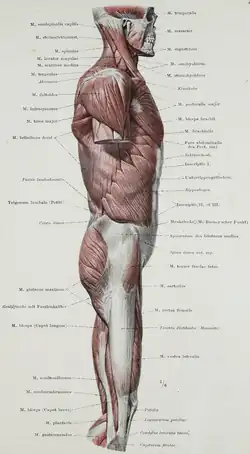

Oberflächenanatomie der Oberschenkelaußenseite. Gluteus maximus durch x gekennzeichnet.

Oberflächenanatomie der Oberschenkelaußenseite. Gluteus maximus durch x gekennzeichnet. -

Gluteus maximus, Ansicht von lateral.

Gluteus maximus, Ansicht von lateral. -